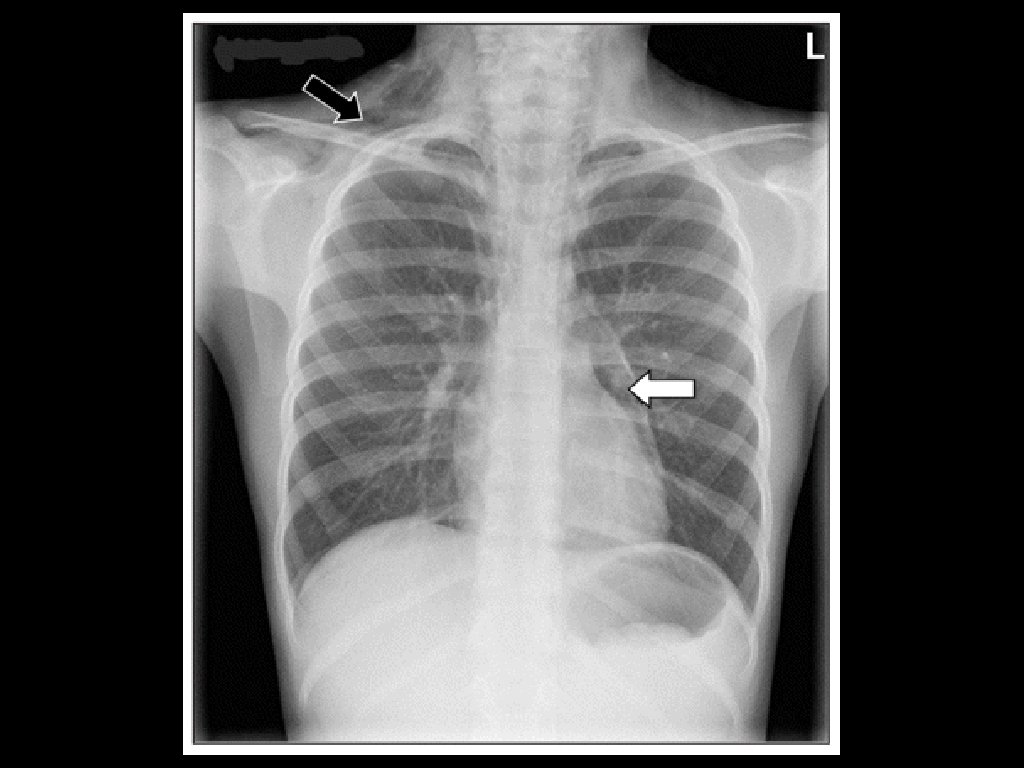

Tension Pneumothorax • Can occur for many reasons including iatrogenic (e. g. from central lines). • Shock and respiratory symptoms due to pneumothorax compressing the mediastinum, resulting in decreased venous return to the heart. • Often secondary to thoracic trauma.

• It can also caused by a simple spontaneous pneumothorax progressing to tension pneumothorax. • Diagnosis is clinical, Don’t wait for the X-ray to make the diagnosis. • Treat with needle decompression while preparing for ED Thoracostomy.